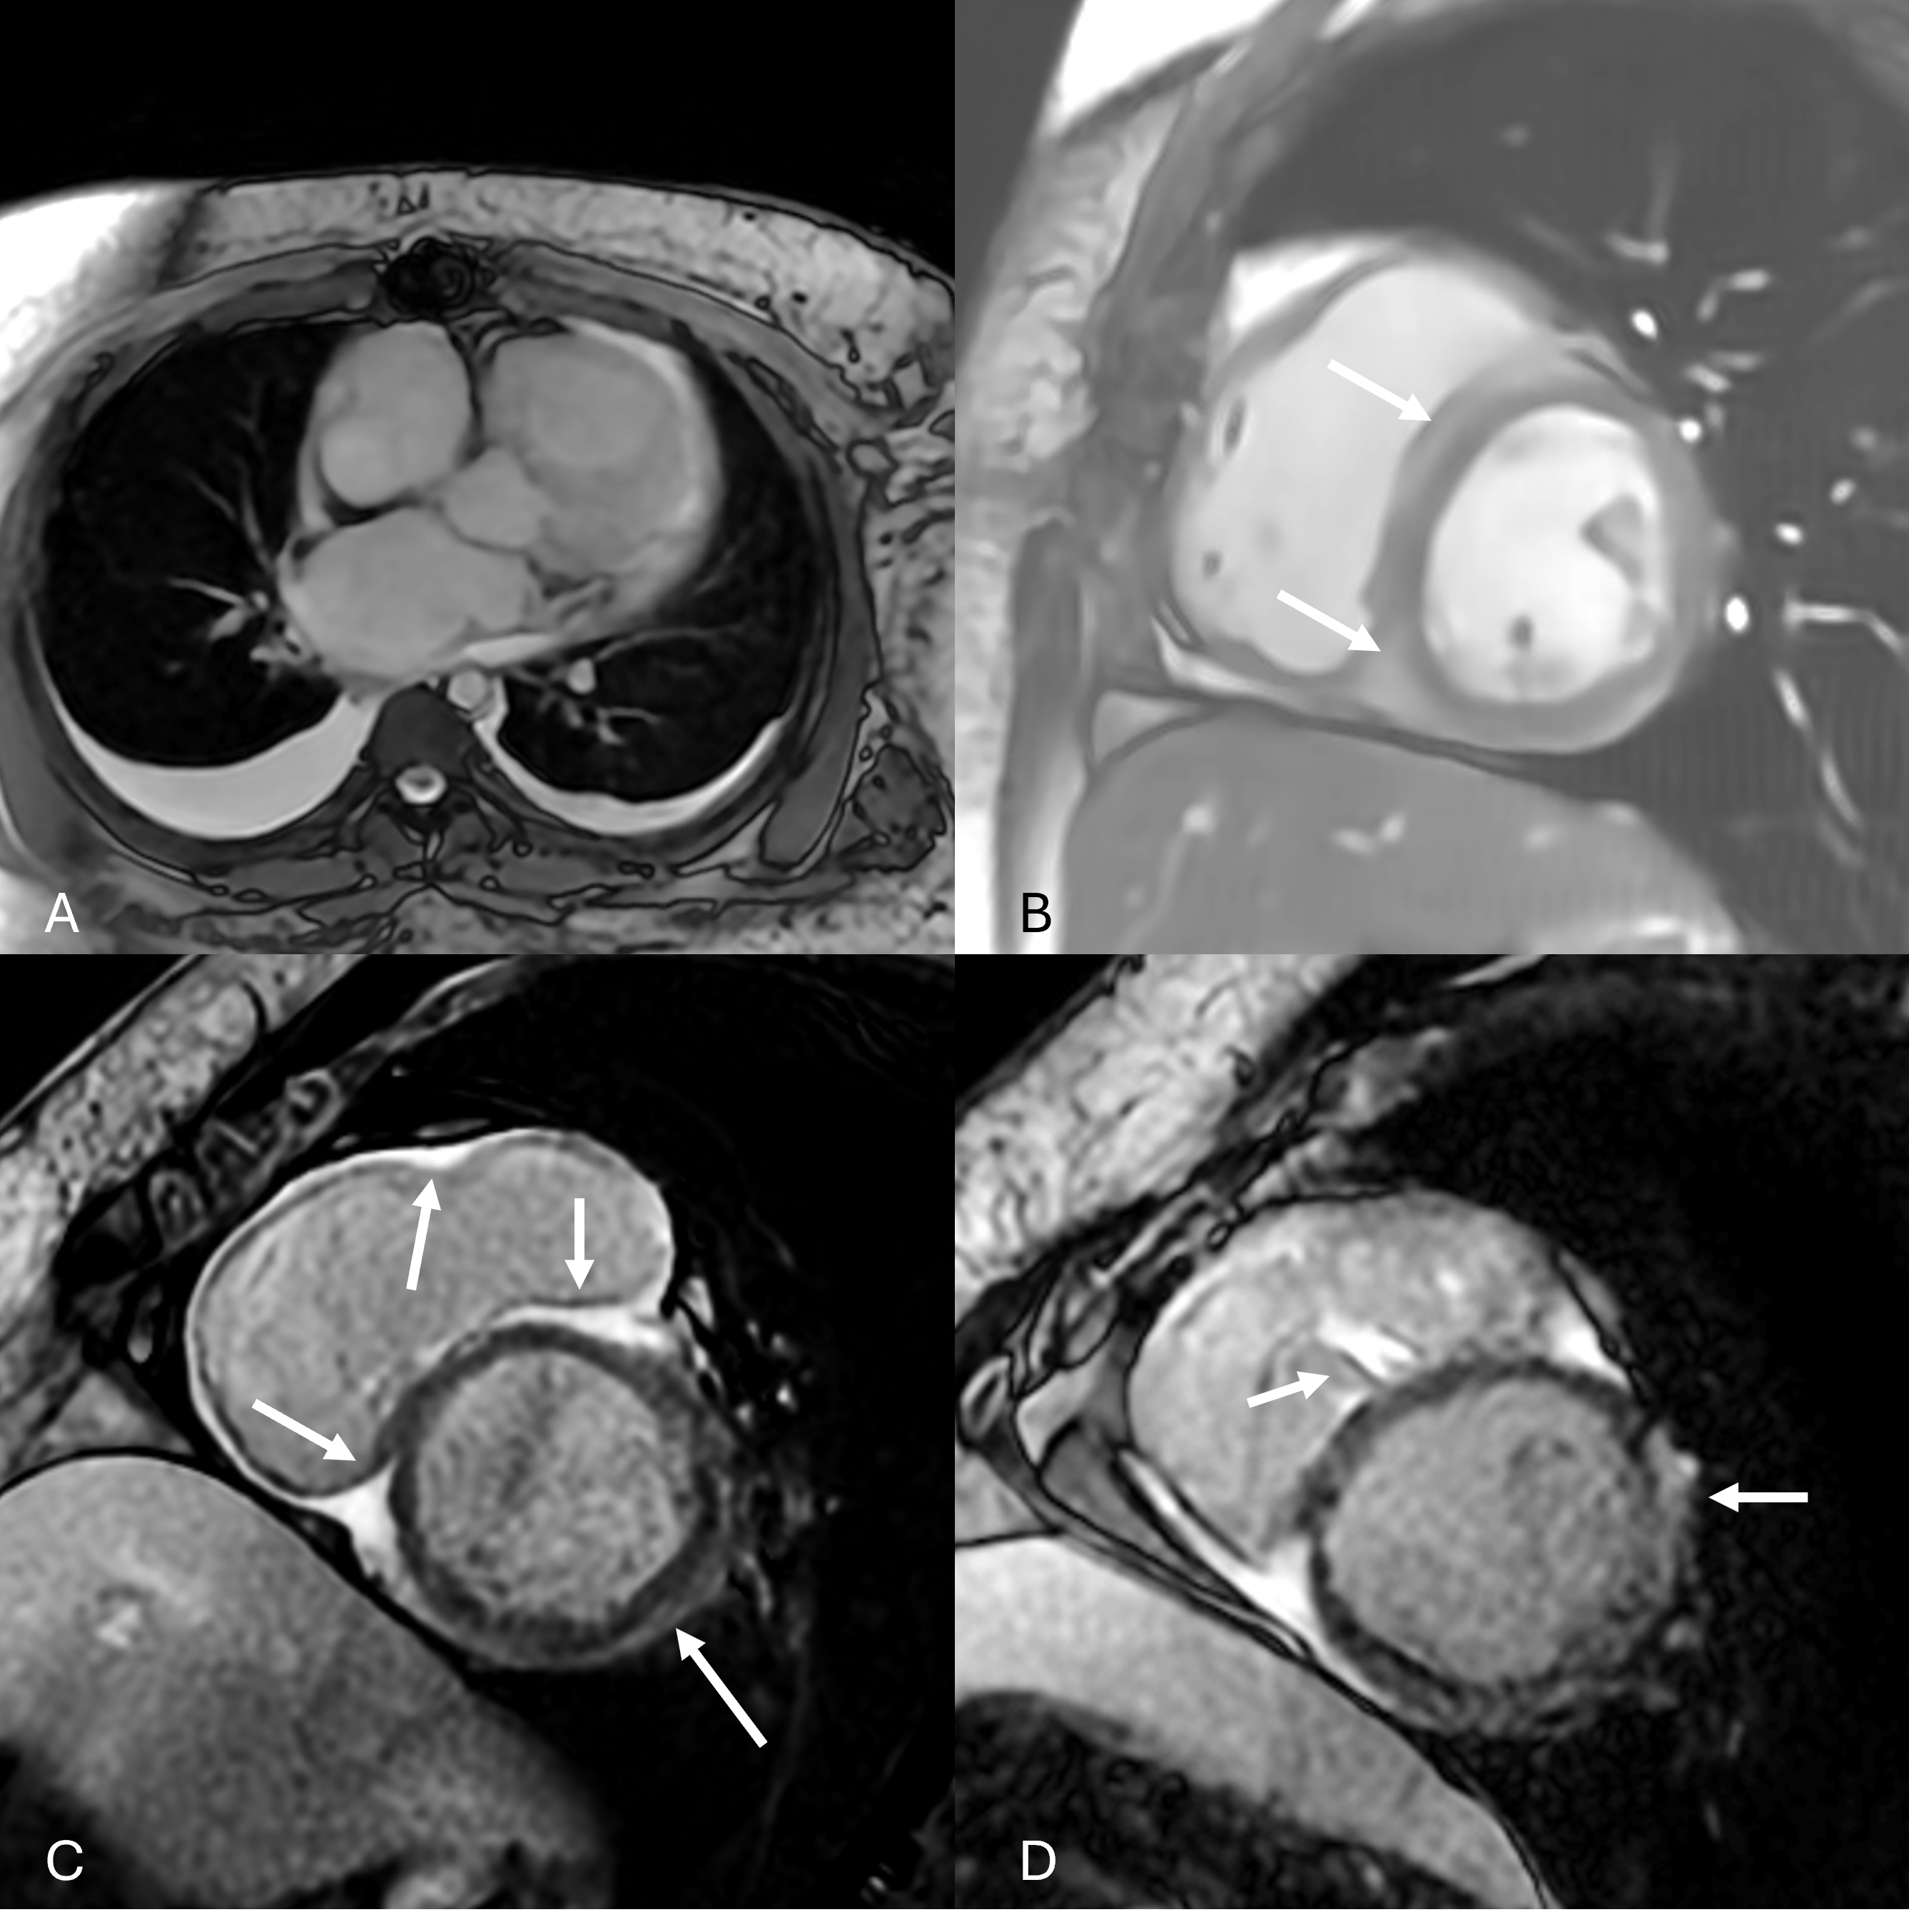

Diagnostic Techniques and Their Most Important Findings: CMR on a 1.5T scanner revealed LVEF 32% and RVEF 31%, bilateral pleural effusions, and hypointensity within the myocardium on bSSFP imaging. Given recent biopsy, inflammation was expected along the septal wall. However, there were several T2 "hotspots" in the LV particularly in the inferior and free walls (T2 of 54-72ms). Significant elevation in T1 and ECV was found in the septum as expected but also in anterior and free walls (ECV of 34-46%). LGE along RV septum was expected but no LV LGE was noted (Fig 1).

Figure 1: Panels demonstrating bilateral pleural effusions (A), and abnormal hypodense appearance of myocardium along right ventricular aspect of intraventricular septum (B, arrows) both on bSSFP imaging, and significant late gadolinium enhancement in the right ventricle, parietal band, and RV septal surface without presence in the LV (C, D, arrows) on LGE imaging.